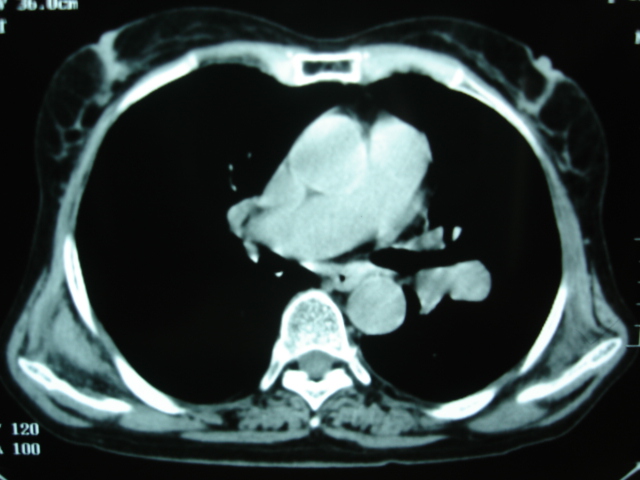

以下是引用卜一在2009-9-7 19:51:00的发言:[br][br] 1 左侧胸内甲状腺占位-多考虑甲状腺腺瘤! 2、左肺门占位-建议增强扫描以便明确性质。 3 慢支并感染! [br]

以下是引用shibing在2009-9-7 20:40:00的发言:[br]左侧胸内甲状腺占位-多考虑甲状腺腺瘤! 2、左肺门占位-建议增强扫描以便明确性质。 3 慢支并感染! [br]